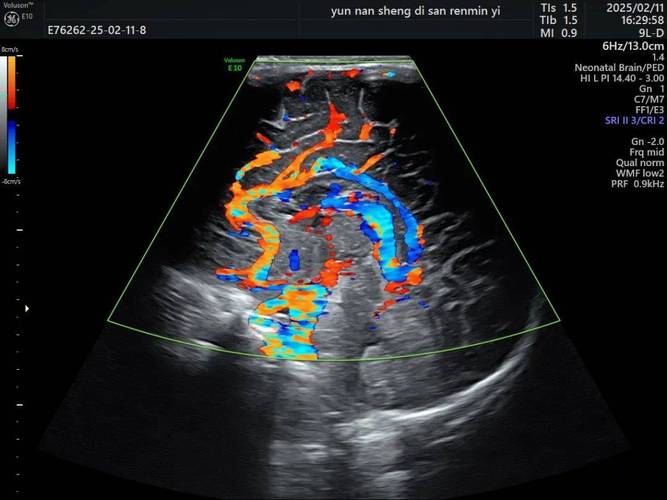

新生儿头颅彩超是一种利用高频声波(超声波)来检查新生儿大脑和头颅结构是否健康的无创、无辐射的影像学检查。

- 彩超作用: 能清晰地发现出血的位置(如脑室内、脑室周围)和范围,是诊断新生儿颅内出血的首选方法。

- 操作简单: 医生会让宝宝侧卧或俯卧,露出柔软的囟门(前囟或后囟),医生会在宝宝的囟门处涂抹一些耦合剂(一种凝胶),目的是让声波能更好地传导。

- 开始检查: 医生会用一个小小的、像手电筒一样的超声探头在囟门处轻轻移动,探头不会给宝宝带来任何疼痛或辐射。

- 实时成像: 医生可以在屏幕上实时看到宝宝大脑的图像,并进行测量和记录。

- 对特定结构显示清晰: 对于前囟未闭的婴儿,通过囟门这个“窗口”,对大脑中央结构(如脑室、基底节等)的显示效果非常好。